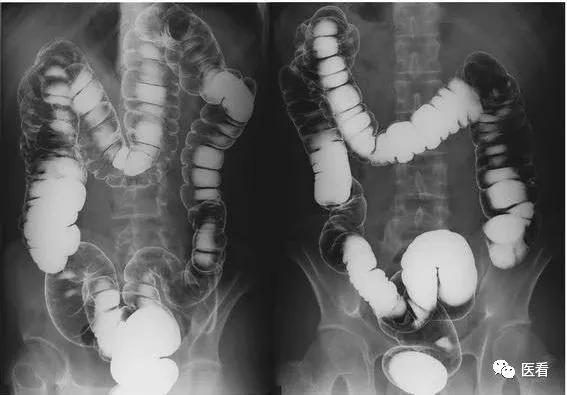

有些增强造影剂影像学检查最好也空腹,因为造影剂会有过敏引起呕吐的风险。内镜检查,如胃镜、肠镜,如果检查前不空腹,食物在胃内,整个胃粘膜根本不能显露清楚,检查就没有了意义。

胃肠镜、喉镜、支气管镜以及经食管超声心动图等内镜检查,因为这些内镜不是需要直接观察胃肠道,就是有可能或直接刺激到消化道导致呕吐,再或者就是需要麻醉,有误吸的风险。

胃肠道造影检查

要求:禁食8-12小时

检查前一天晚上10点以后禁食,同时暂停内服药物。次日早上空腹到放射科接受检查。如不禁食,胃内容物可影响胃肠形态的观察;服用某些药物可能影响胃肠道功能。